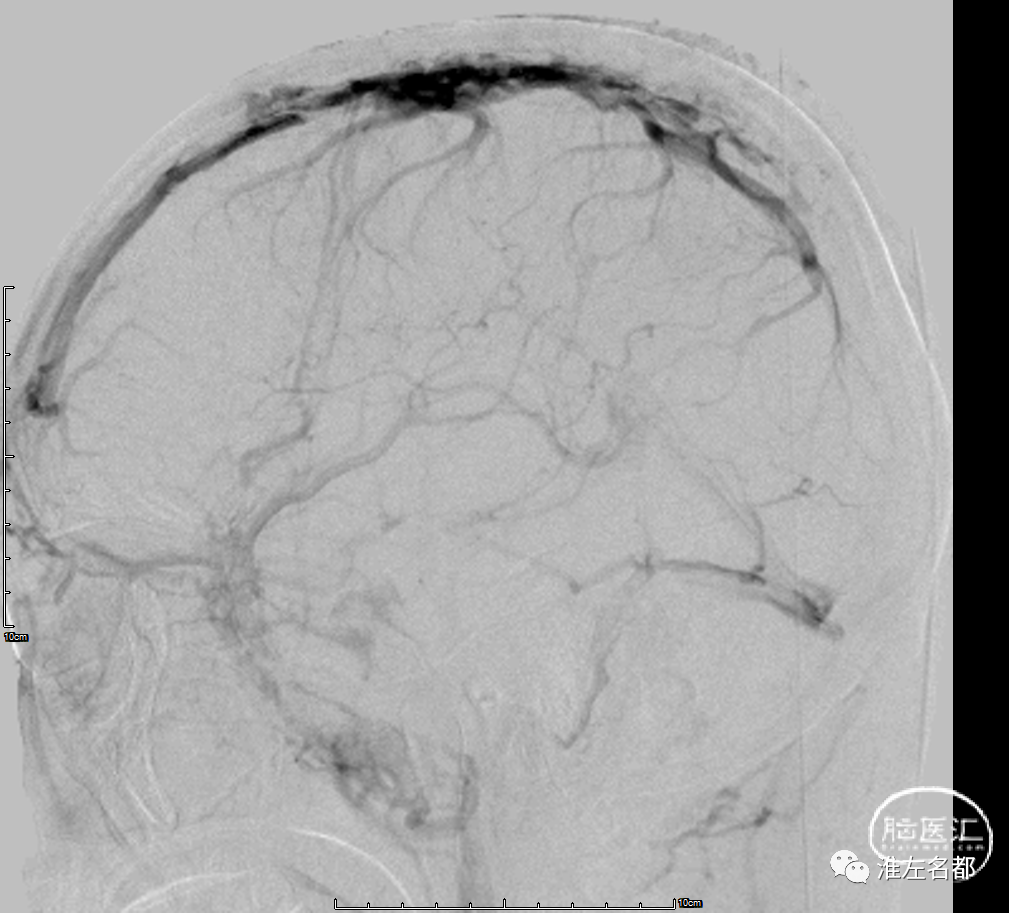

经右侧颈动脉造影

术后经右侧颈动脉造影

术后经左侧颈动脉造影

介入治疗术后DSA:上矢状窦引流恢复,右侧横窦显影改善。

第二次介入治疗术前DSA(经左侧颈动脉造影):右侧乙状窦显影较前改善,上矢状窦中后部闭塞。

第二次介入治疗术后DSA:上矢状窦和右侧横窦-乙状窦显影通畅,引流良好。